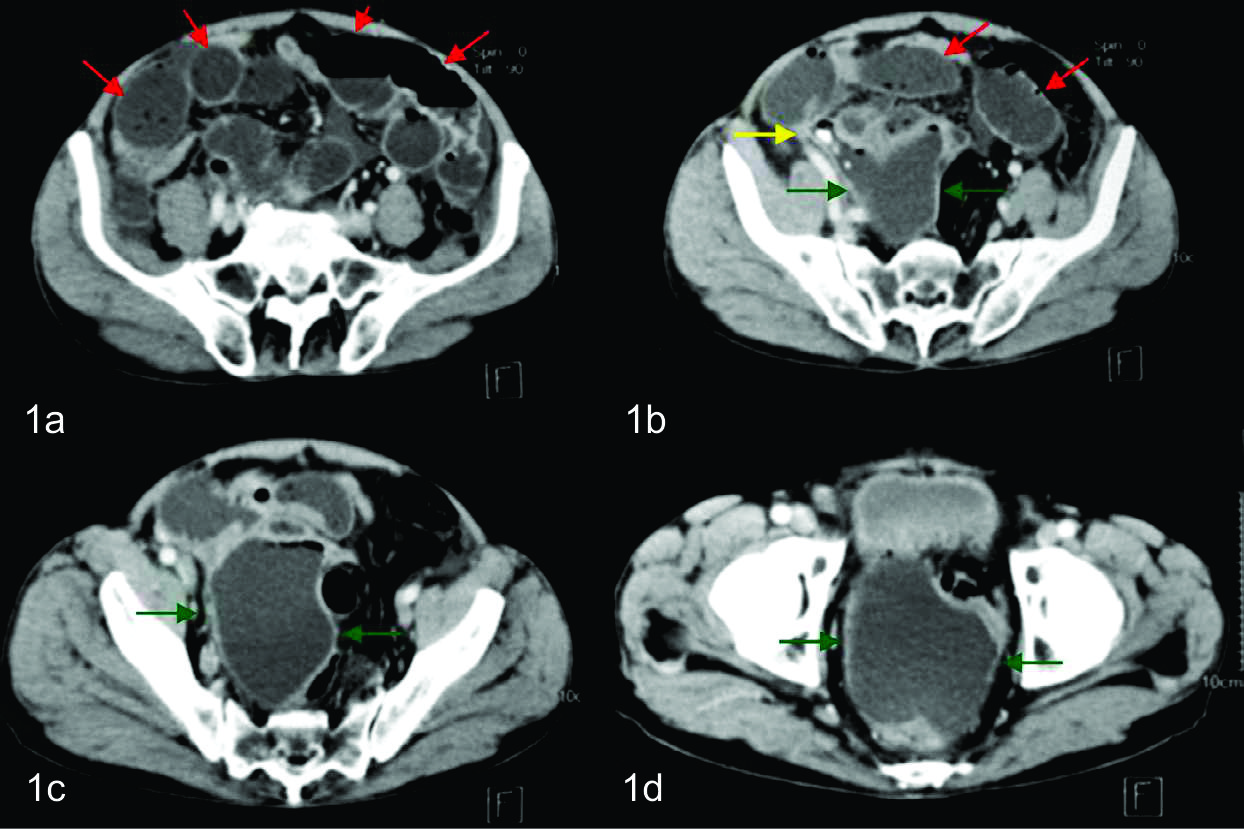

De la paraclínica humoral se destaca la presencia de leucocitosis de 14000 x 10 3 ul. Con el planteo de cuadro agudo de abdomen por parte del equipo médico tratante, se le solicita una tomografía de abdomen y pelvis, la cual fue realizada con MC i/v en fase portal.

En la adquisición inicial se identifica una colección de paredes finas a nivel de fosa iliaca derecha, en relación a la raíz del mesenterio, inmediatamente por delante de los grandes vasos. La misma presentaba gas en el sector no declive y alteración de la densidad de la grasa adyacente, de aspecto inflamatorio.

En los cortes más caudales se reconoce al ciego en su topografía habitual y de él se observa emerger de su pared posterior, al apéndice cecal, el cual es de aspecto patológico, tomando contacto con la colección antes descripta. Con el planteo de apendicitis aguda complicada con colección infectada se discute junto con cirujano tratante la eventual posibilidad de poder realizar tratamiento percutáneo, el cual se determinó que era pasible de ser efectuado en este paciente. Se realizó nuevamente bajo guía tomográfica con el paciente en decúbito supino. Se procedió a topografiar el sitio de abordaje en piel a nivel de flanco derecho y se coloco drenaje multipropósito 12 F bajo técnica de Seldinger, el cual se dejo abierto a bolsa colectora con llave de tres vías. El material obtenido fue purulento, algo hemorrágico, con grumos, del cual se tomaron muestras para análisis bacteriológico, cultivando gérmenes gram negativos. En el control tomográfico posterior, a los cinco días de colocado el drenaje, se necesitó un reposicionamiento del mismo, pudiendo evacuar totalmente la colección residual en la evolución. Luego de 15 días de colocado el drenaje, con levados diarios en los últimos 7 días, una vez resuelta la colección, sin elementos clínicos ni paraclínicos humorales de infección, se decide retirar el drenaje, presentando el paciente una excelente evolución.